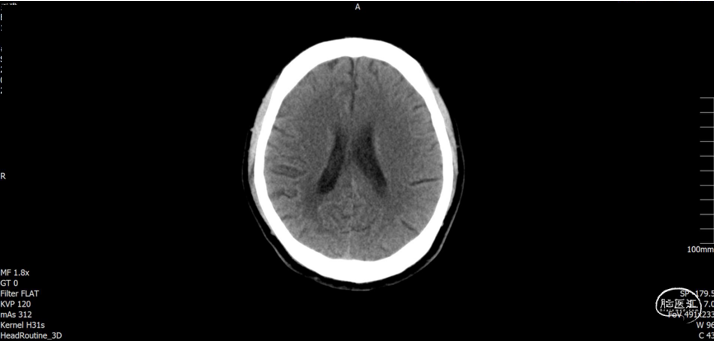

术后随访

术后CT

![]()

术后随访

术后72h CT,复查后拔除硬膜下引流管

术后72h胸部 CT

术后1周 CT

术后70天CT